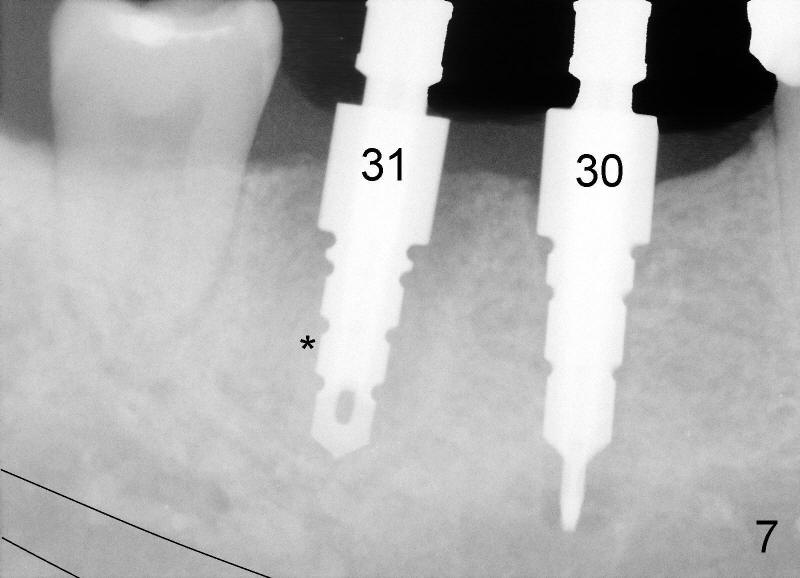

Six weeks post-extraction, a straight incision is made along the crest of #30/31. Without raising flap, #15 surgical blade, bone scalpels (4,5,6 mm wide) and bone blades (4,5.5,7.5 mm wide) ) (Fig.4 white line (illustration); Tatum Surgical) are used to expand the septum buccolingually (arrows). Then round tapered osteotomes (Fig.5 black circle (illustration)) are used to expand the septum circumferentially (arrows). Bone expansion with osteotomes alternates with sequential drills using irrigation. Fig.6 shows 4x17 and 4x14 mm drills placed in sockets #30 and 31, respectively. It appears that osteotomies are placed somewhat distally. The drill #31 is distal to the septum (*).

After adjustment, next drills (5x17, and 5x14 mm for #30 and 31) are located more appropriately relative to neighboring teeth (Fig.7) and also in some distance from the inferior alveolar canal (black lines). The septum of #31 is now distal to the drill for #31. Finally 6x17 and 7x14 mm Tatum tapered implants are placed with certain degree of initial stability (Fig.8). Black dashed lines represent the inferior alveolar canal. Fig.9 is taken immediately post-implant placement.